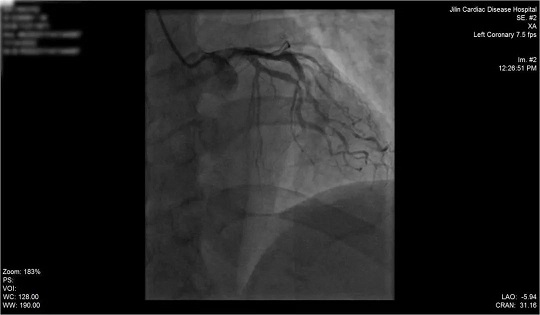

术后冠脉造影

入院后,我院心内科团队争分夺秒进行救治,第一时间为患者行冠状动脉造影检查,锁定冠状动脉左前降支为罪犯血管,心内科Sirbu医生当机立断,为患者先进行冠状动脉血栓抽吸术,将血管中血栓吸出,随后成功于病变处植入1枚支架。从入院到抢救成功,仅用时50分钟。

患者术后状态良好,穿刺点无出血、渗血,无不适主诉,生命体征平稳,于病情好转后出院。